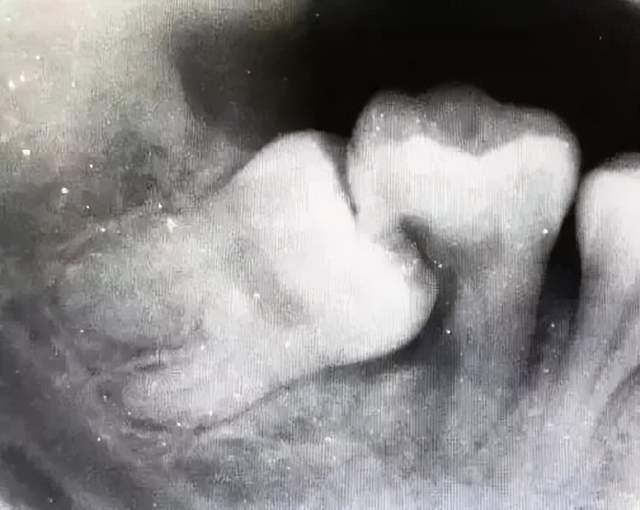

空间困境导致位置异常:智齿作为最后萌出的牙齿,常因空间不足而受阻,形成阻生、倾斜或错位。这种异常位置本身就会对周围软组织形成慢性刺激和挤压。

清洁困境引发细菌感染:智齿位于口腔最深处,日常清洁本就困难。一旦位置不正,其与邻牙之间极易形成难以彻底清洁的“死角”,食物残渣和牙菌斑在此持续堆积,为细菌提供了温床,从而反复引发 “智齿冠周炎”(即牙冠周围软组织发炎)。

清洁死角内的细菌不仅侵害智齿本身,更会侵蚀相邻的第二磨牙,导致其出现龋坏(蛀牙)、牙根吸收或牙周损伤,可能连带损失一颗健康的重要牙齿。